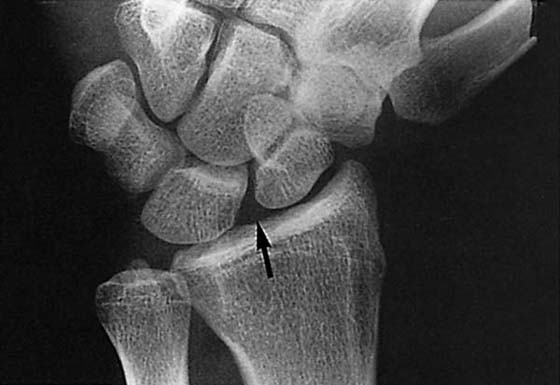

images

Figure 13-4 This posteroanterior view of the wrist shows a fracture of the proximal third of the scaphoid (arrow) with an associated cyst.